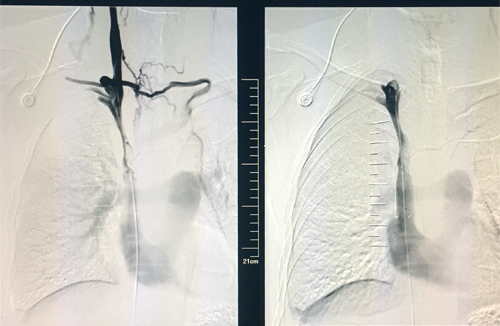

48岁的章先生近期因咳嗽、胸闷入临床医学院/附属医院就诊,不幸确诊为肺癌晚期,伴上腔静脉重度狭窄,逐渐出现颜面部及上肢浮肿,胸壁浅表静脉扩张,并有显著胸闷及颜面部肿胀。为提高患者生活质量,延长患者生存期,该院呼吸内一科介入组决定为其实行上腔静脉支架置入,经术前充分评估,术中精细操作,以20分钟完成支架置入。术后,上腔静脉再通,胸壁“蚯蚓”消失,症状瞬间缓解,达到立竿见影的治疗效果,赢得患者及家属的高度称赞。